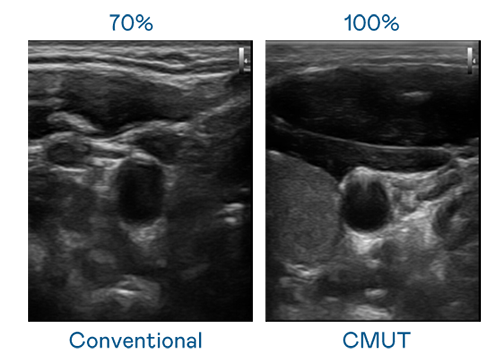

CMUT 技术是一种用电容式微机电元件来产生超音波讯号的技术。与传统 PZT 压电式技术相比,CMUT 频宽增加 30%,更宽频的超音波讯号让影像解析度大幅提升,是实现高影像品质医疗超音波扫描、促进精准医疗发展的关键技术。

大频宽带来超清晰影像

超音波影像的解析度高低,首先取决于探头能发出的讯号频宽。1xBET CMUT 可提供高清晰的超音波讯号,提供高频宽、高灵敏度、影像纹理细节更高的超音波影像,协助医护人员缩短影像判读时间及利用精准的医疗影像进行诊断。